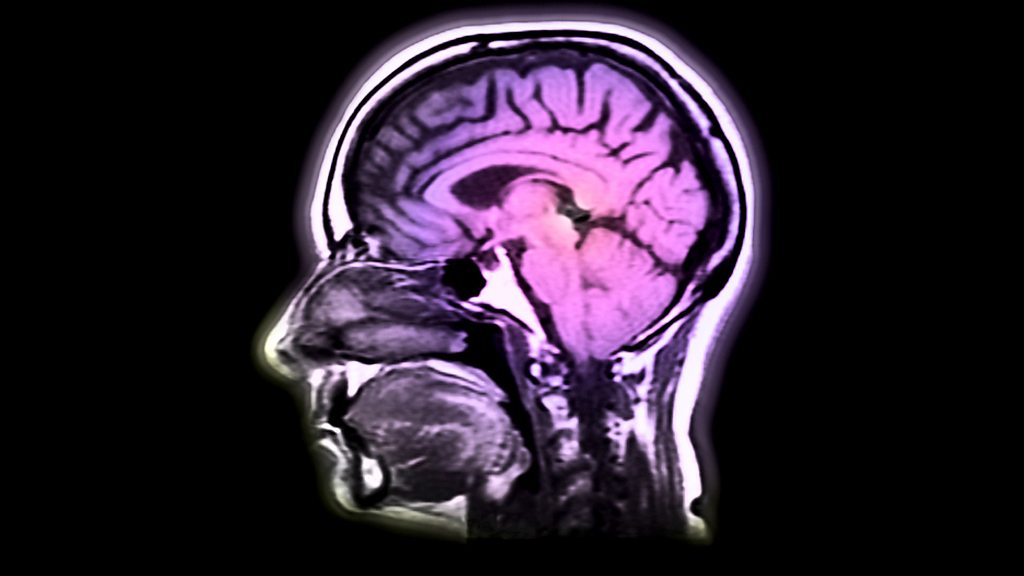

With Jane Garvey. New research has shown that far from being muddled, the brains of those aged between 40 and 60 could be in peak condition. The science writer Barbara Strauch talks to Jane about the latest findings on the middle-aged brain. A recent court case has highlighted the lack of clarity in the laws surrounding sex workers operating out of brothels. Jane discusses the implications of the case and whether this might force more women back onto the streets. Ines de la Fressange was recently voted the most stylish woman in Paris. As her guide to Parisian chic is published, she shares her style secrets with Jane. And, the artist Rose Hilton turns 80 this year. As an exhibition of her work opens in London, we visit her Cornish studio.